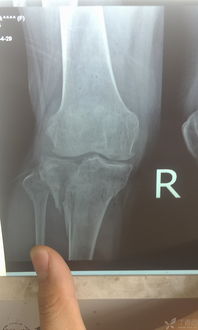

胫骨平台是位于胫骨上端的一个平台,与股骨的髁部形成膝关节。胫骨平台骨折是指胫骨平台部位发生的骨折,可能是由于直接撞击、跌倒或扭伤等原因引起。根据骨折的严重程度和位置,可分为多种类型,如单纯骨折、粉碎性骨折等。

并非所有胫骨平台骨折都适合保守治疗。以下情况可以考虑采用保守治疗:

无移位的胫骨平台骨折

胫骨平台关节面塌陷小于2mm